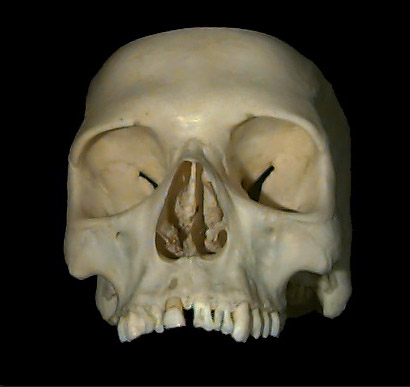

Human Skull

Click to go to interactive quicktime video with panning capabilities.

From the QTVR Anatomical Resource